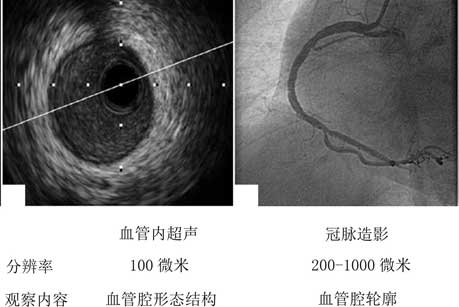

血管内超声是一种先进的介入检查技术,是将微型化的超声换能器通过导管技术置入血管腔,经电子成像系统可以直接观察到血管壁的结构和血管腔内的病变情况。与冠脉造影不同,血管内超声属于腔内影像技术,逐渐成为新的冠状动脉疾病诊断的金标准。

血管内超声在病变的诊断以及在指导介入治疗中较冠脉造影有更多的优势:能够在术前精准地测量冠状动脉的狭窄程度;评价斑块的性质;帮助术者制定和优化冠心病介入治疗方案;在介入术中能够早期发现介入治疗中可能存在的并发症;评估扩张后支架与冠脉管壁贴壁是否良好以及预后情况;提高手术的安全性和治疗效果。

(血管内超声和冠脉造影的比较)